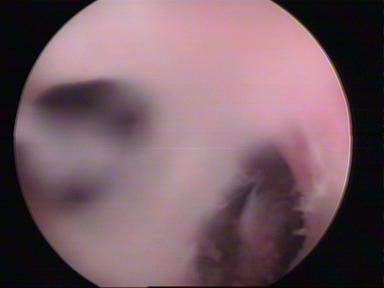

Septum Resection

Septum UterusDIAGNOSTIC LAPAROSCOPY

Operative hysteroscopy can treat many of the abnormalities found during diagnostic hysteroscopy. Operative hysteroscopy is similar to diagnostic hysteroscopy except that narrow instruments are placed into the uterine cavity through a channel in the operative hysteroscope. Fibroids, scar tissue, and polyps can be removed from inside the uterus. Some structural abnormalities, such as a uterine septum, may be corrected through the hysteroscope.